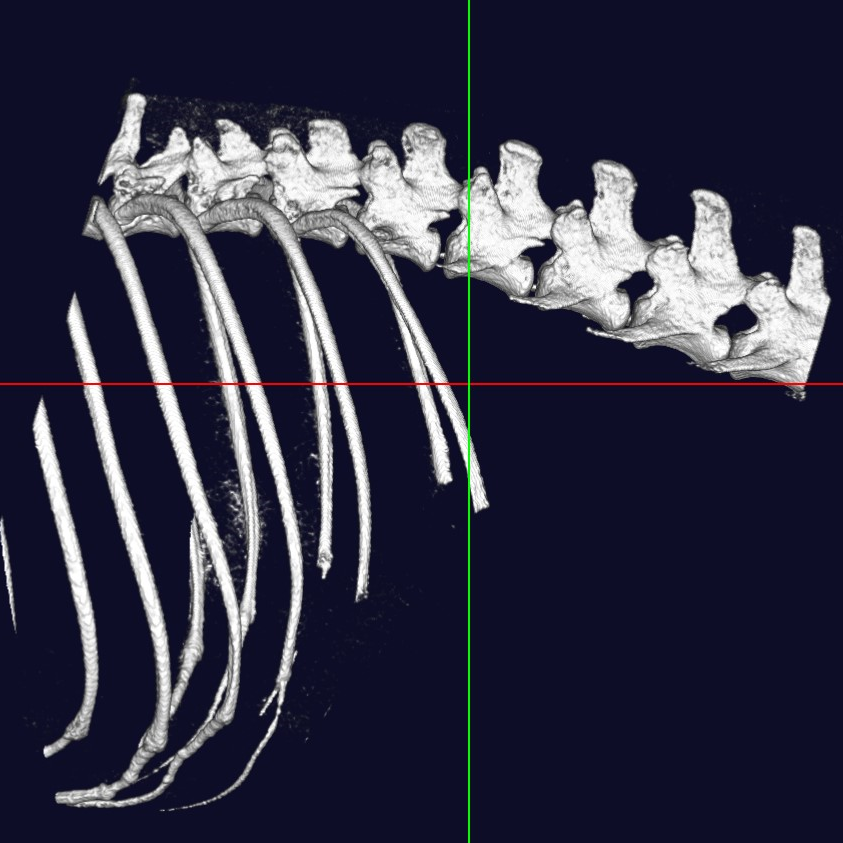

中・小型動物用3DマイクロCT

CTとはコンピューター断層撮影(Computed Tomography)の略で、X線を用いて身体の横断像(輪切り)を撮影することが出来ます。立体3D画像が得られるのも特徴で、主に骨格の異常や臓器系の異常部位、腫瘍性病変の把握に利用されます。

当院では「中・小型動物用3DマイクロCT」を導入しています。エキゾチックペットから猫・小型犬まで撮影可能です。

高画質で立体的に見ることで、レントゲンや超音波検査では分からない病態の診断や、構造が複雑な部位の細かい評価が可能です。

体の断層像に加え立体3D画像の作成が可能

事前に病変部位やその周囲の臓器との関係性を把握することで、より正確で安全な外科手術につながります。

また、飼い主様へお話しする際に、立体の3D画像のため病変のイメージがしやすくなります。

脊椎・脊髄・筋骨格

- 椎間板ヘルニア

- 骨折

- 脱臼

犬 椎間板ヘルニア